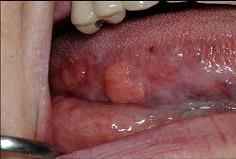

问题 以下关于舌癌(如图)的叙述,哪项是错误的 ( )

选项 A.舌根部癌可向茎突后及咽后部的淋巴转移 B.以鳞状细胞癌多见 C.转移途径多为直接浸润和种植转移 D.常发生早期颈部淋巴结转移 E.多发生于舌缘,恶性程度高

答案 C